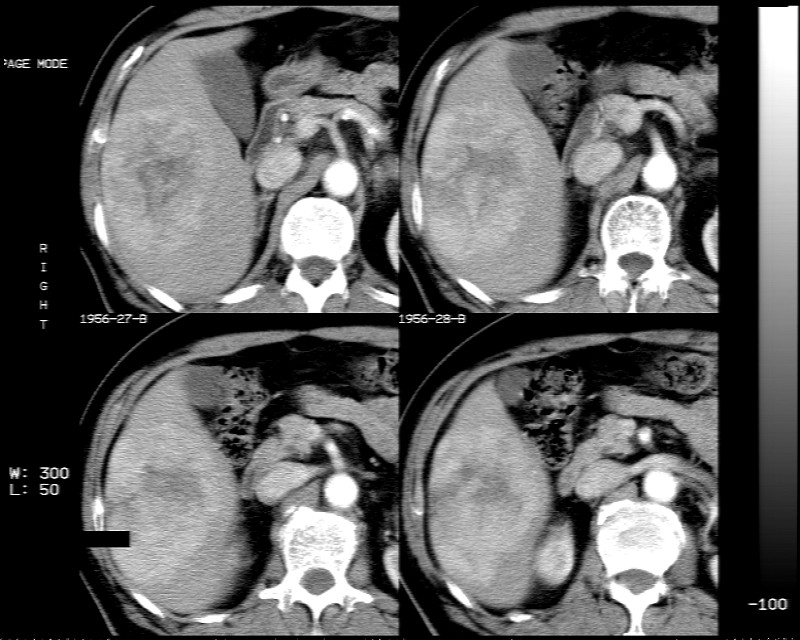

肝脏右叶块状低密度影,增强后动脉期明显强化,门脉期强化减低,延迟期病灶又成低密度。考虑肝细胞癌。我认为比较典型。

低密度肿块,动脉期明显强化,可见星状低强化区,门脉期强化向中心扩展,但病灶动脉期强化最明显,门脉期及平延迟期强化减低,结合病只考虑巨大局灶性结节增生,血管瘤不除外

肝右叶巨大占位性病变,平扫呈低密度改变,增强扫描动脉期病灶周围强化,门脉期强化未退出,延时期病灶周边强化与肝实质接近,病灶中心在各期均可见星状不强化区;首先考虑局灶性结节增生可能性大,其次为血管瘤。肝癌不能完全排外(不首先考虑肝癌是因为强化不支持快进快出特点)。

平扫示:肝右后叶下段内见类圆形略低密度占位病灶,边界尚清楚,最大径约为102×71mm,ct值31~41hu。

动态增强扫描示:动脉期病灶显著不均性强化,病灶强化密度高于肝实质;平衡期病灶呈等密度;延迟扫描病灶密度略低于肝实质;三期均见占位病灶内有裂隙状无强化影。肝内胆管无扩张,腹膜后未见肿大淋巴结。

拟诊:肝右后叶下段内占位性病变,考虑为肝结节样增生。

建议进一步检查(mri/或穿刺活检),不排外肝ca。